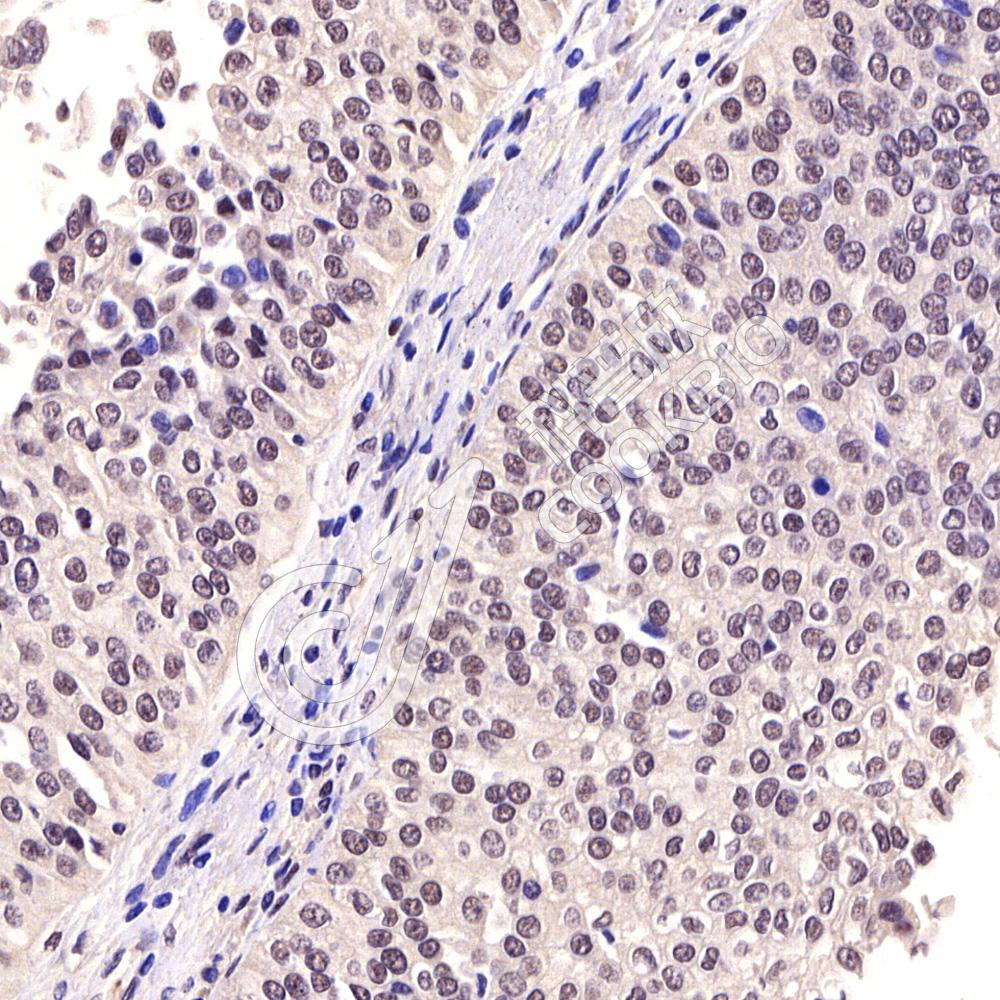

IHC检测Melanoma gp100蛋白(货号 K5450480).

样品: 人黑色素瘤, 4%多聚甲醛 (货号KSG1101) 固定12-24小时.

抗原修复: Tris-EDTA抗原修复液(pH 9.0) (货号KSG1203), 水浴100℃, 25分钟.

—抗: 1: 1000稀释, 4℃ 孵育过夜.

二抗: S-vision免疫组化多聚二抗(山羊抗小鼠), 即用型(货号KB3903), 室温孵育20分钟.